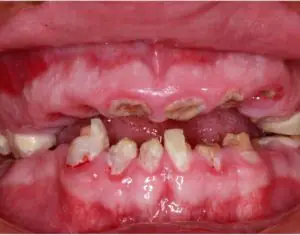

A Liverpool mother says she was left with severe dental problems after undergoing cosmetic treatment at a dental clinic in Dubai she found on social